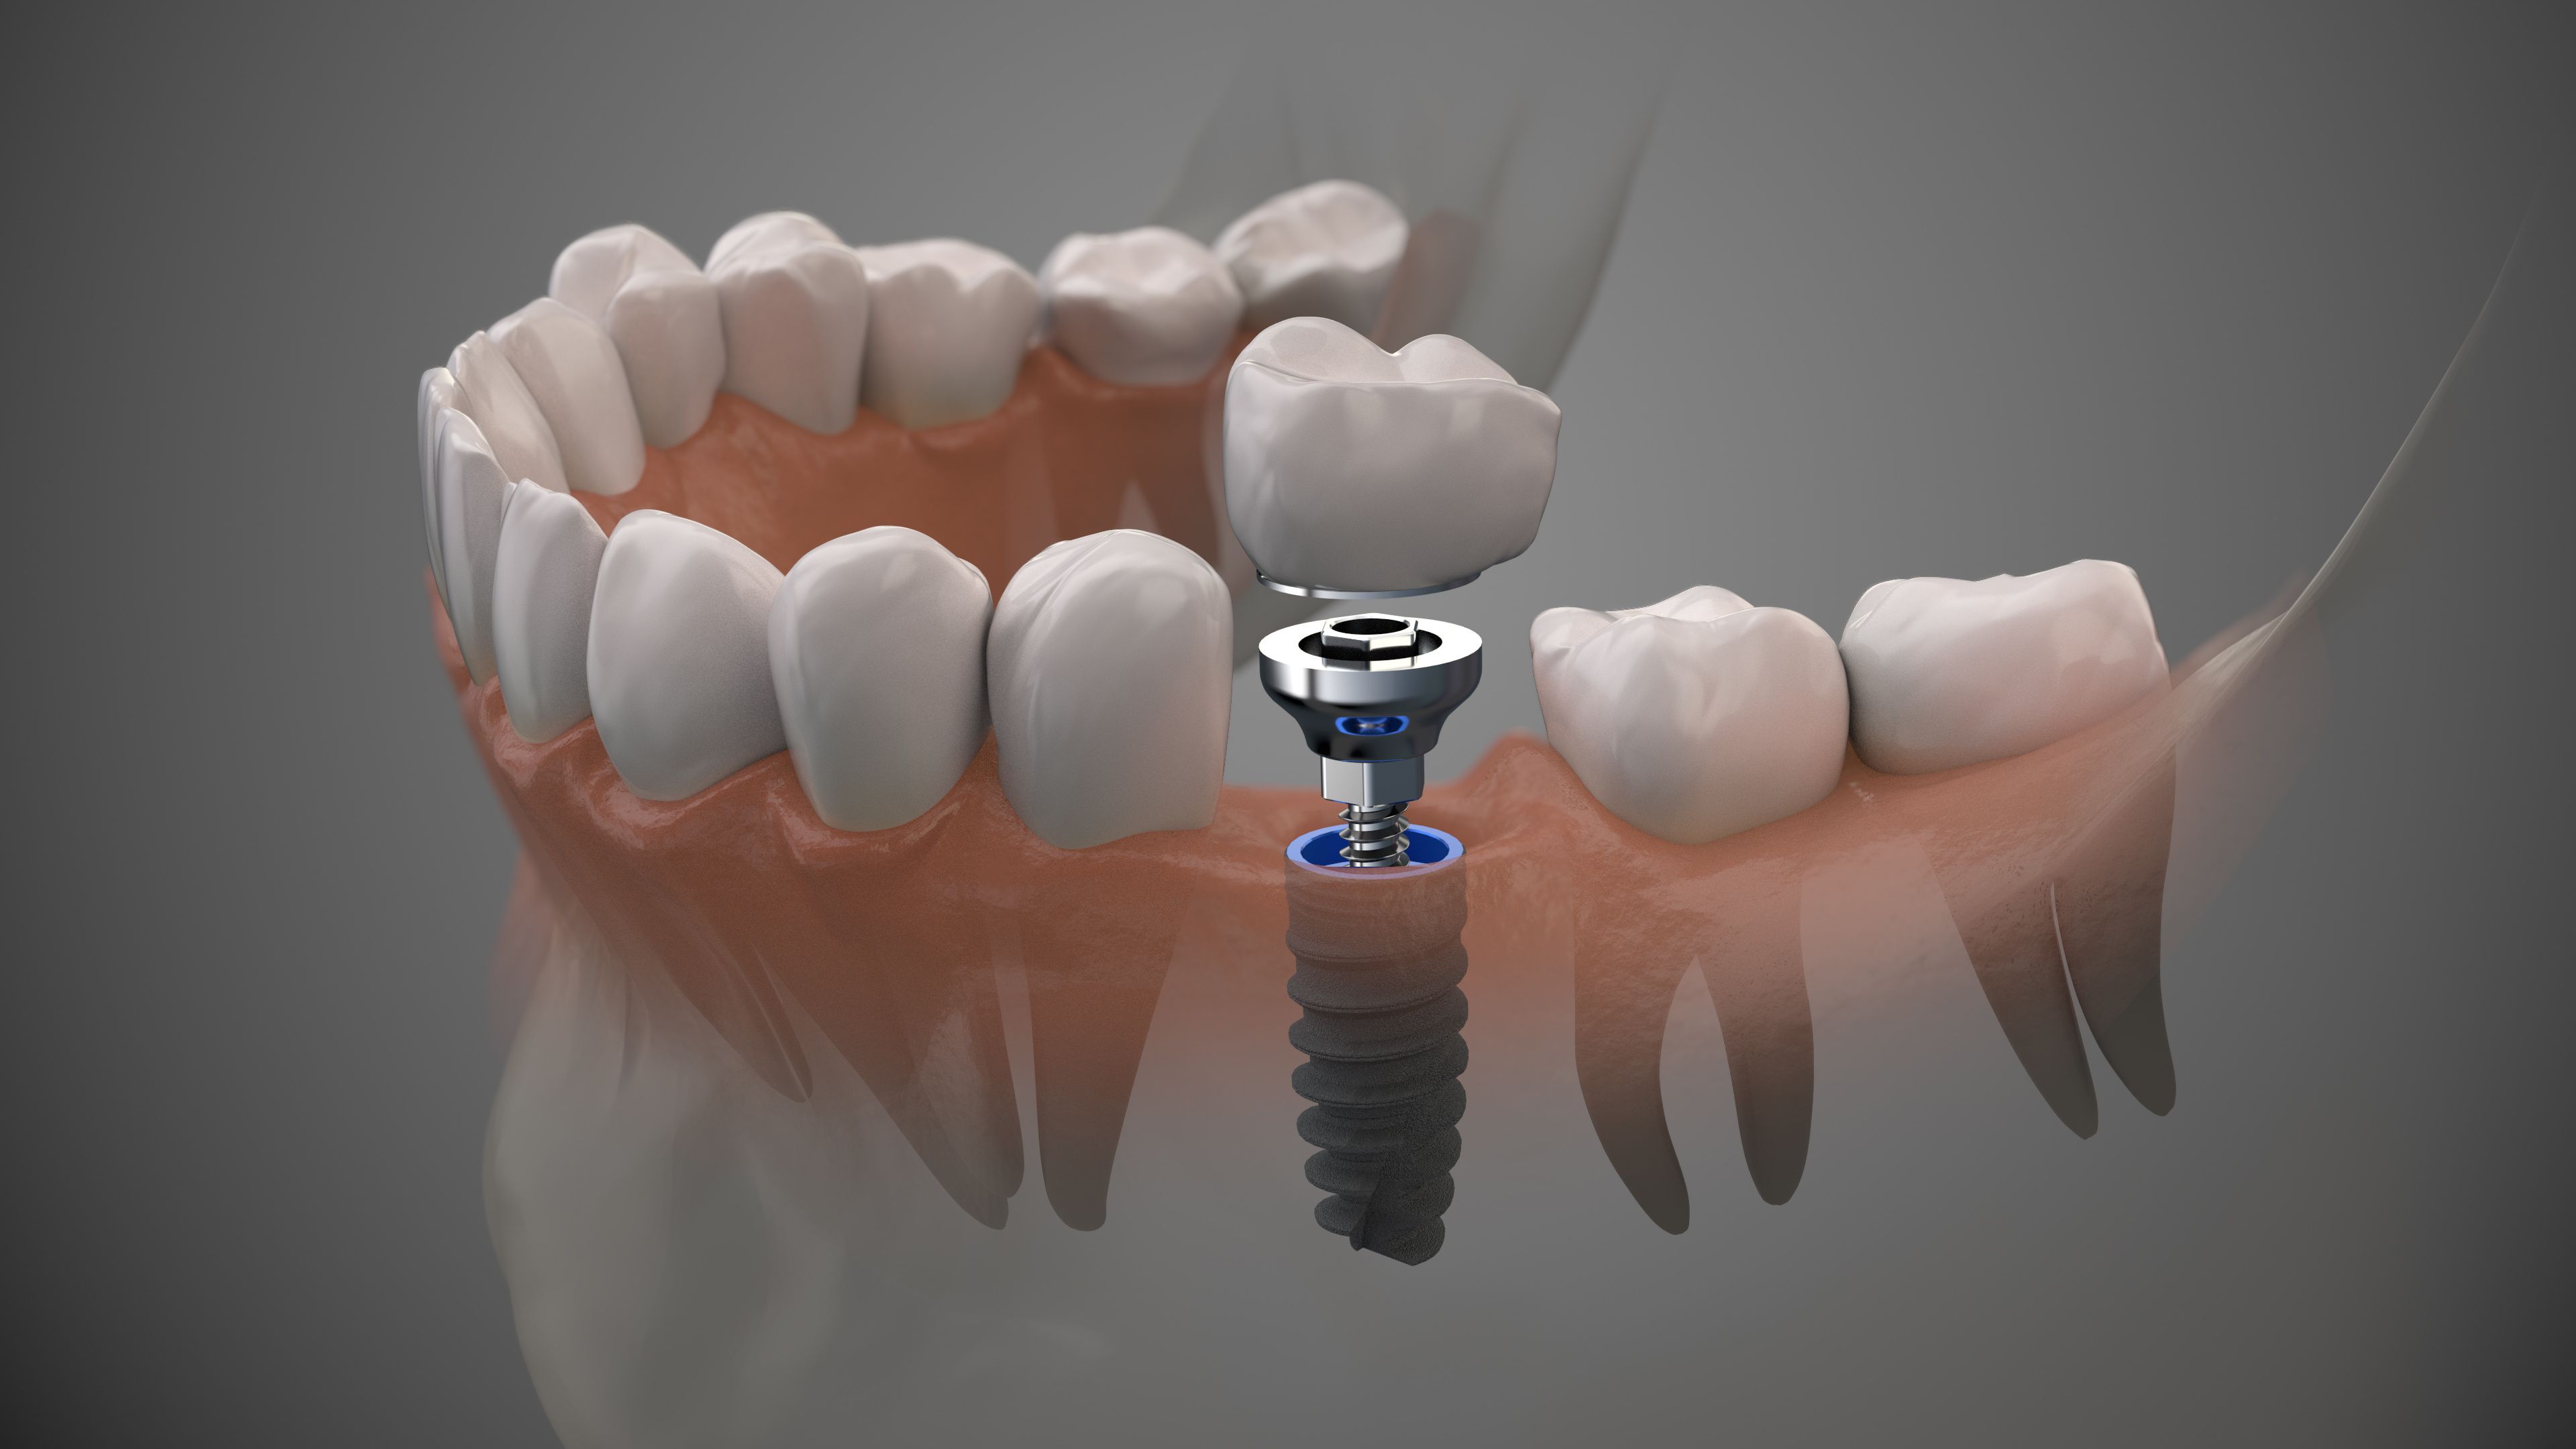

Современные коронки на зубные импланты: виды и фото-примеры